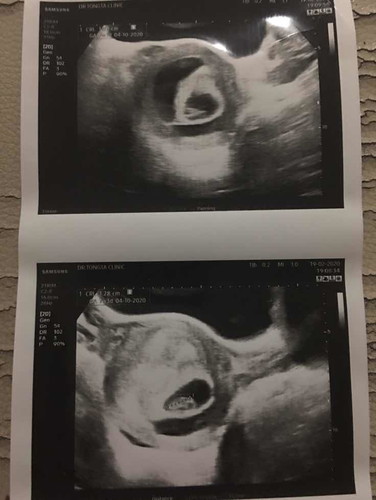

7week รกลอกตัว

หมอบอกโอกาสที่น้องจะไม่อยู่ก็มีสูงเพราะรกลอกตัวไปเยอะมาก ? มีแม่คนไหนเจอประสบการณ์นี้บ้างค่ะ จิตตกมากค่ะ และก็กังวลมากด้วย